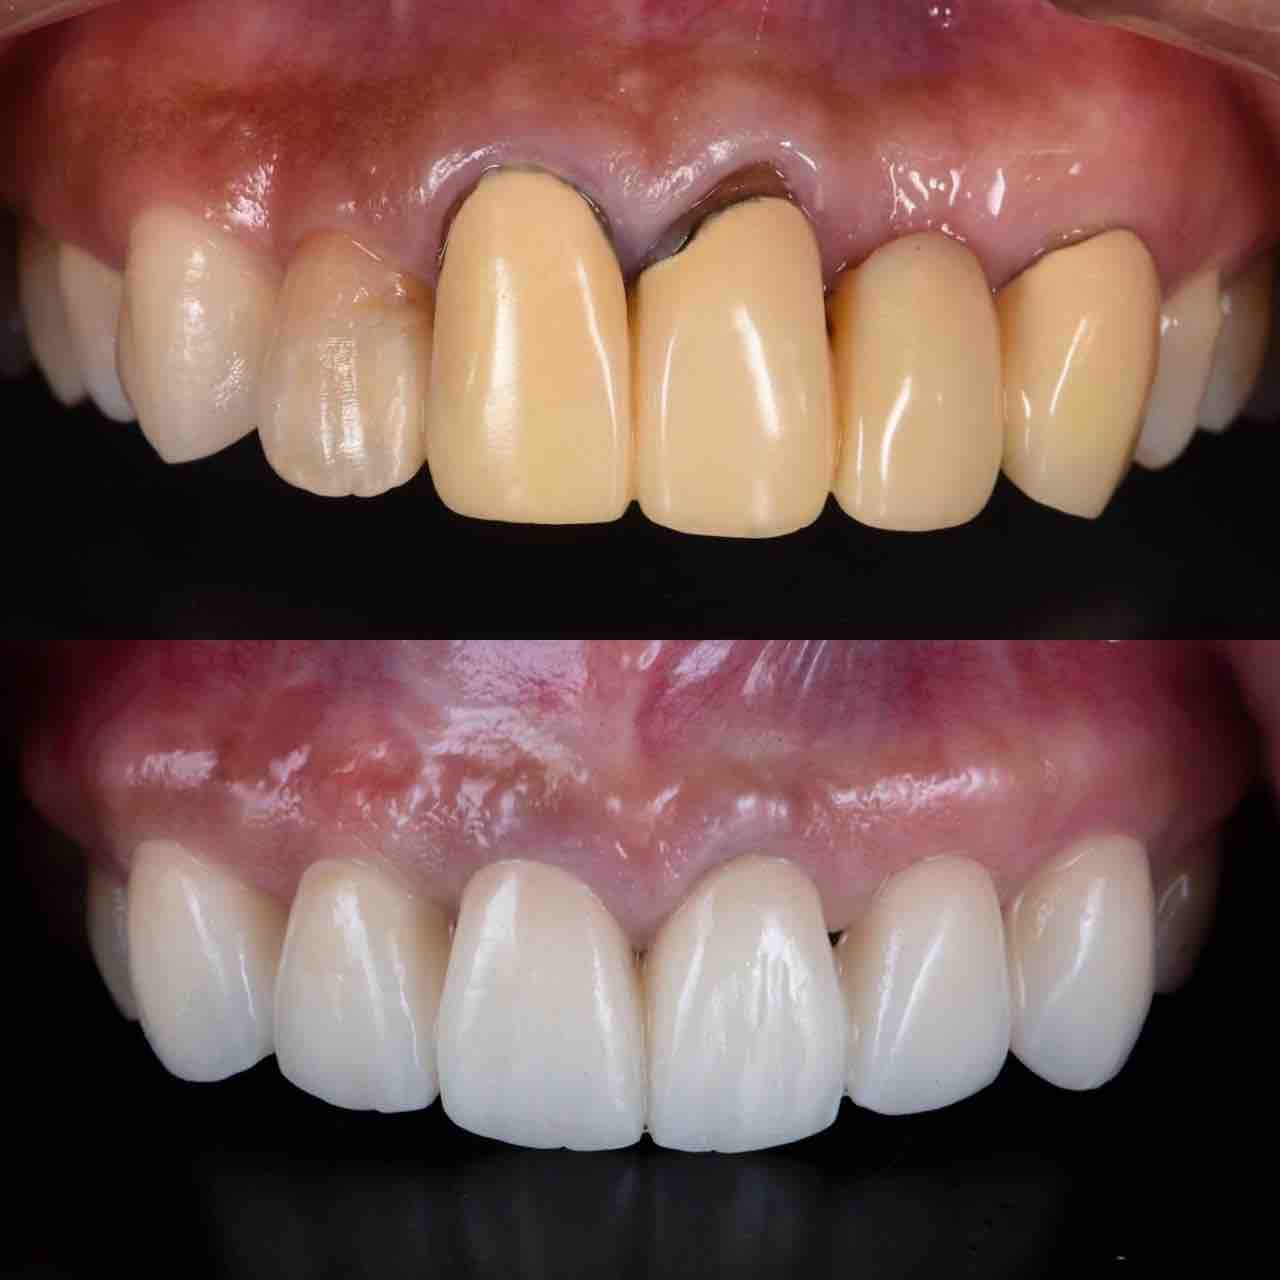

ðÌî»õ²Ê¾ÉÎ㢠ÀèÅ··ç»¶ºÀµ¥¤¥ó¥×¥é¥ó¥È

ðÌî»õ²Ê¾ÉÎã¡¶ºÀµ¥¤¥ó¥×¥é¥ó¥È¥»¥é¥ß¥Ã¥¯